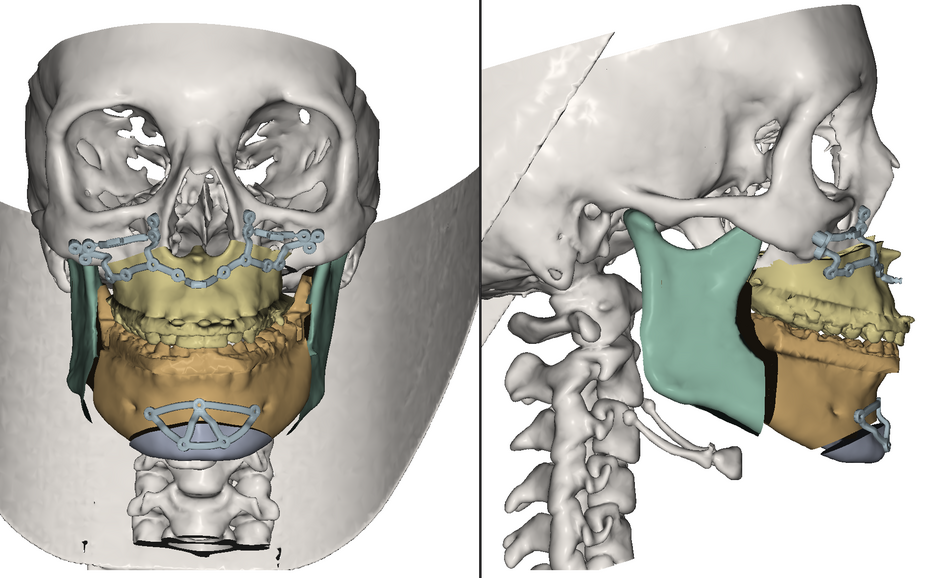

Aufgrund der komplexen anatomischen Strukturen des Kopf- und Gesichtsschädels stellen chirurgische Eingriffe auf diesem Gebiet eine besondere Herausforderung dar. Daher erfordern diese Eingriffe eine detaillierte Vorbereitung und einen strukturierten Behandlungsplan. Konventionell wird der operative Eingriff, ausgehend vom klinischen Befund des Patienten, nach entsprechender Bildgebung durchgeführt. Unsere Forschungsgruppe befasst sich mit dem Einsatz von technischen Möglichkeiten, um die Patienten-Bilddaten transparenter und das operative Ergebnis vorhersehbarer zu machen. So werden nach der Bildgebung noch weitere Planungsschritte eingeschaltet, bevor der Eingriff stattfindet. Die Datensätze des Patienten werden nach Import und Fusionierung genutzt, um eine präzise Analyse des klinischen Befundes vorzunehmen. Anschließend kann der dreidimensionale Datensatz beliebig oft bearbeitet werden und die Schritte des operativen Eingriffs simuliert werden, so dass Patienten-spezifische Implantate schon vor dem Eingriff hergestellt werden können. Durch eine solche Planung kann der komplette chirurgische Eingriff mit allen Simulationsschritten im Vorfeld virtuell durchlaufen werden, so dass der Patient anschließend in nur einem Eingriff optimal versorgt wird. Derzeit arbeiten wir in unserer Forschungsgruppe zusammen mit Industriepartnern (BrainLab, KLM Medizintechnik, Materialise) an einer solchen Planungsplattform, um unseren Patienten die bestmögliche Behandlung zukommen zu lassen. Die Planungsschritte sollen dann dem Patienten direkt an seinem Patientenbett über das Smartphone oder Tablet veranschaulicht werden. Unter anderem entwicklen und evaluieren wir auch eine computer-assistierte Untersuchungsmethode zur Diagnostik und Analyse von Antiresorptiva-assozierter Kiefernekrose. Zudem befasst sich unsere Forschungsgruppe mit der Entwicklung einer virtuellen Dysgnathie-Software, um Bisslagenkorrekturen, Weichteilvorhersagen und Profilanalysen berechnen zu können (IPS Case designer).

Die ablative und traumatische Gesichtschirurgie kann mit dramatischen Veränderungen der Gesichtsgeometrie assoziiert sein, so dass ein sekundärer Korrektureingriff zur Wiederherstellung der Funktion und Ästhetik notwendig sein kann. Mit konventionellen Behandlungsmöglichkeiten ist oftmals keine originalgetreue Rekonstruktion betroffener Strukturen möglich, weshalb unsere Forschungsgruppe daran arbeitet, den Einsatz der computer-assistierten Chirurgie in diesem Feld voranzutreiben. Dazu werden sogenannte Patientenspezifische Implantate so designt, dass zuerst das ästhetisch wünschenswerte Endergebnis simuliert wird, indem das Ausmaß des Weichteilgewebes dargestellt wird und von diesem Ziel ausgehend rückwarts geplant wird, wie die knöchernen Strukturen rekonstruiert werden müssen. Diese Art der Planung unterscheidet sich deutlich von anderen Planungen und ist auch weitaus komplexer. Trotz hochauflösender CT und MRT-Aufnahmen kann nicht auf jede kleine Weichgewebsstruktur und deren elastisches Verhalten eingegangen werden, aber durch die Planung kann dieses Problem durch eine gewisse Überkorrektur kompensiert werden. Mit Hilfe der Finite-Elemente-Methodik können die besagten Strukturen so miteinander verknüpft werden, dass das komplexe Zusammenwirken der Strukturen annähernd simuliert werden kann und somit die dynamischen Veränderungen durch die einzelnen Arbeitsschritte ersichtlich werden. Durch das Verfahren des Rapid Prototypings (Adaptive Herstellungsverfahren) können anschließend patientenspezifische Titan und Kunststoff Konstrukte fabriziert werden. Wir beschäftigen uns fortwährend mit der Optimierung solcher funktionellen Implantate, Schnitt und Bohrschablonen.